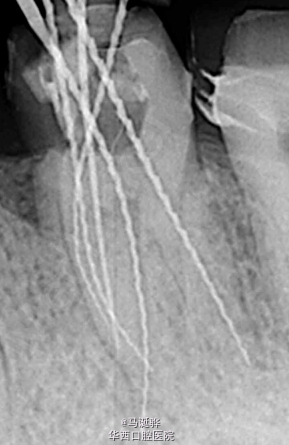

任何一个口腔医生都捅过根管。根管形态有多百变,有多复杂,有多美妙,就不用我细说了。尤其是磨牙,有时简直叫我们发狂。今天我们就细数一下那些变异加变态的根管吧。 1,切牙双根管。这个还好,一般能够准确找到两个根管。难度系数★★ 2,MB2,上颌磨牙常见根管,发生率近70%,有时比较细,不易察觉。难度系数★★★ 接下来开始我们的重头戏 3,MB3。光有MB2还不止,还有MB3……比起MB2,MB3更加需要细心和耐心了。难度系数★★★★